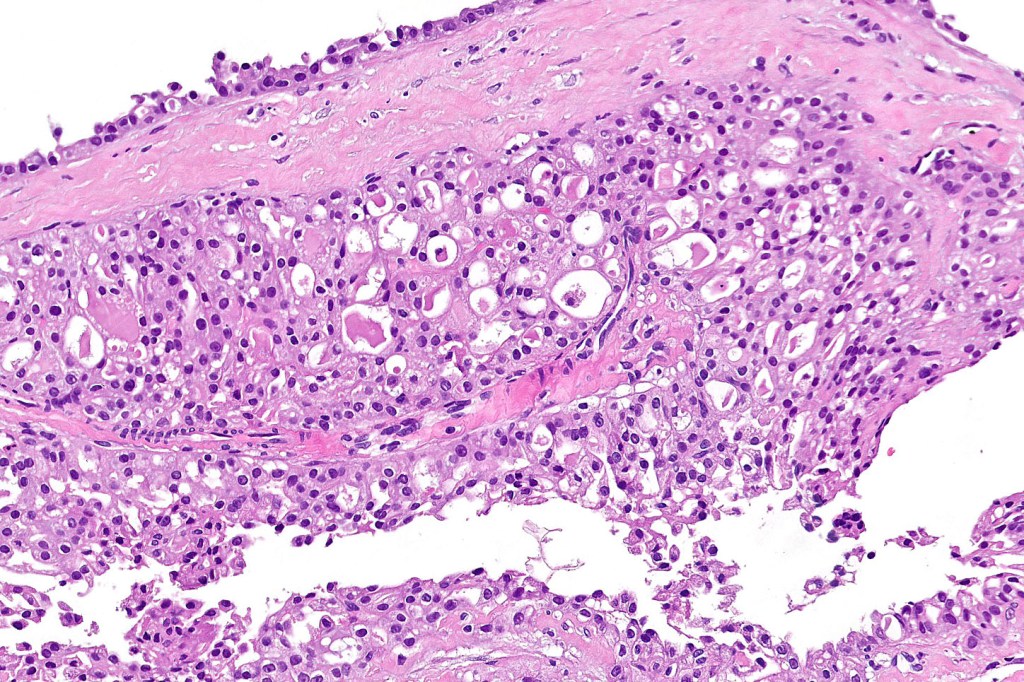

•Solid or cystic circumscribed or infiltrative dermal nodule

•Microcystic, tubular & solid patterns

•Vacuolated/granular/bubbly eosinophilic cytoplasm

•DPAS +ve luminal content

•Low grade atypia, mitoses very sparse, absence of perineural infiltration, lymphovascular invasion or necrosis